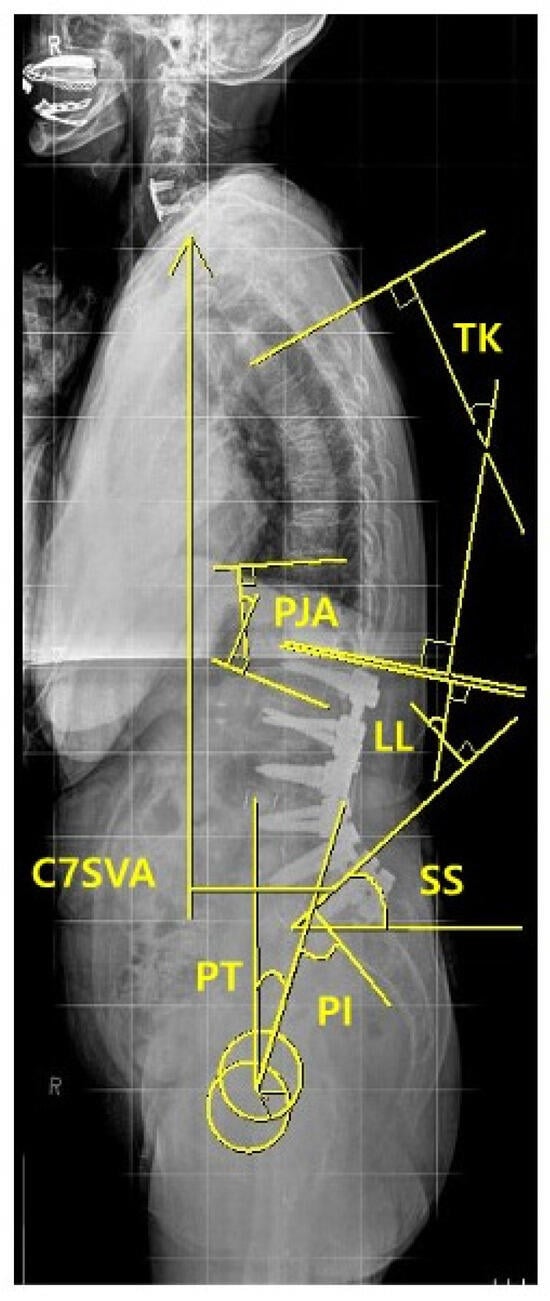

| PJK | Proximal junctional kyphosis |

| PJA | Proximal junctional angle |

| ASD | Adult spinal deformity |

| TK | Thoracic kyphosis |

| TLK | Thoracolumbar kyphosis |

| LL | Lumbar lordosis |

| PT | Pelvic tilt |

| SS | Sacral slope |

| PI | Pelvic incidence |

| SVA | Sagittal vertical axis |

| TK (°), mean ± SD | 7.6 ± 14.3 | 13.9 ± 12.7 | 0.153 |

| TLK (°), mean ± SD | 0.75 ± 0.9 | 0.67 ± 1.0 | 0.082 |

| PJA (°), mean ± SD | 2.98 ± 8.0 | 1.99 ± 12.2 | 0.583 |

| LL (°), mean ± SD | 7.2 ± 24.7 | 20.2 ± 24.5 | 0.115 |

| SS (°), mean ± SD | 23.0 ± 8.5 | 30.1 ± 12.3 | 0.057 |

| PT (°), mean ± SD | 34.0 ± 7.2 | 25.8 ± 13.0 | 0.032 * |

| PI (°), mean ± SD | 56.9 ± 7.0 | 55.5 ± 10.9 | 0.663 |

| C7 SVA (mm), mean ± SD | 92.0 ± 48.5 | 85.1 ± 43.4 | 0.720 |

| Immediate (3 months) postoperative parameters | |||

| TK (°), mean ± SD | 20.7 ± 8.4 | 19.9 ± 17.3 | 0.876 |

| TLK (°), mean ± SD | 23.5 ± 9.9 | 8.7 ± 12.2 | <0.001 * |

| PJA (°), mean ± SD | 20.9 ± 7.7 | 10.7 ± 8.1 | <0.001 * |

| LL (°), mean ± SD | 43.8 ± 13.5 | 45.9 ± 9.4 | 0.569 |

| SS (°), mean ± SD | 32.0 ± 9.4 | 35.6 ± 8.1 | 0.215 |

| PT (°), mean ± SD | 24.1 ± 11.2 | 18.7 ± 8.6 | 0.092 |

| PI (°), mean ± SD | 55.8 ± 7.4 | 53.7 ± 7.0 | 0.376 |

| C7 SVA (mm), mean ± SD | 49.9 ± 38.9 | 37.3 ± 35.6 | 0.303 |